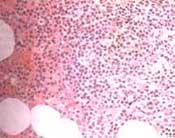

La paciente fue valorada por Hematología considerándose necesario practicar estudio inmuno-histoquímico en las biopsias de las masas endobronquiales (Figura 5), además, practican aspirado y biopsia de médula ósea que informa infiltrado linfoplasmocítico que resalta con el CD79a, con células IgM positivas, predominio de cadenas ligeras lambda e índice de proliferación bajo (5% con el marcador Ki-67) con lo que se concluye el diagnóstico de linfoma linfoplasmocítico B (Macroglobulinemia de Waldenström) (Figuras 6A y B).

Figuras No. 6A y 6B: Biopsia de médula ósea con infiltrado linfoplasmocítico

monoclonal que resalta con el CD79A. HE 20X y CD79A 20X.